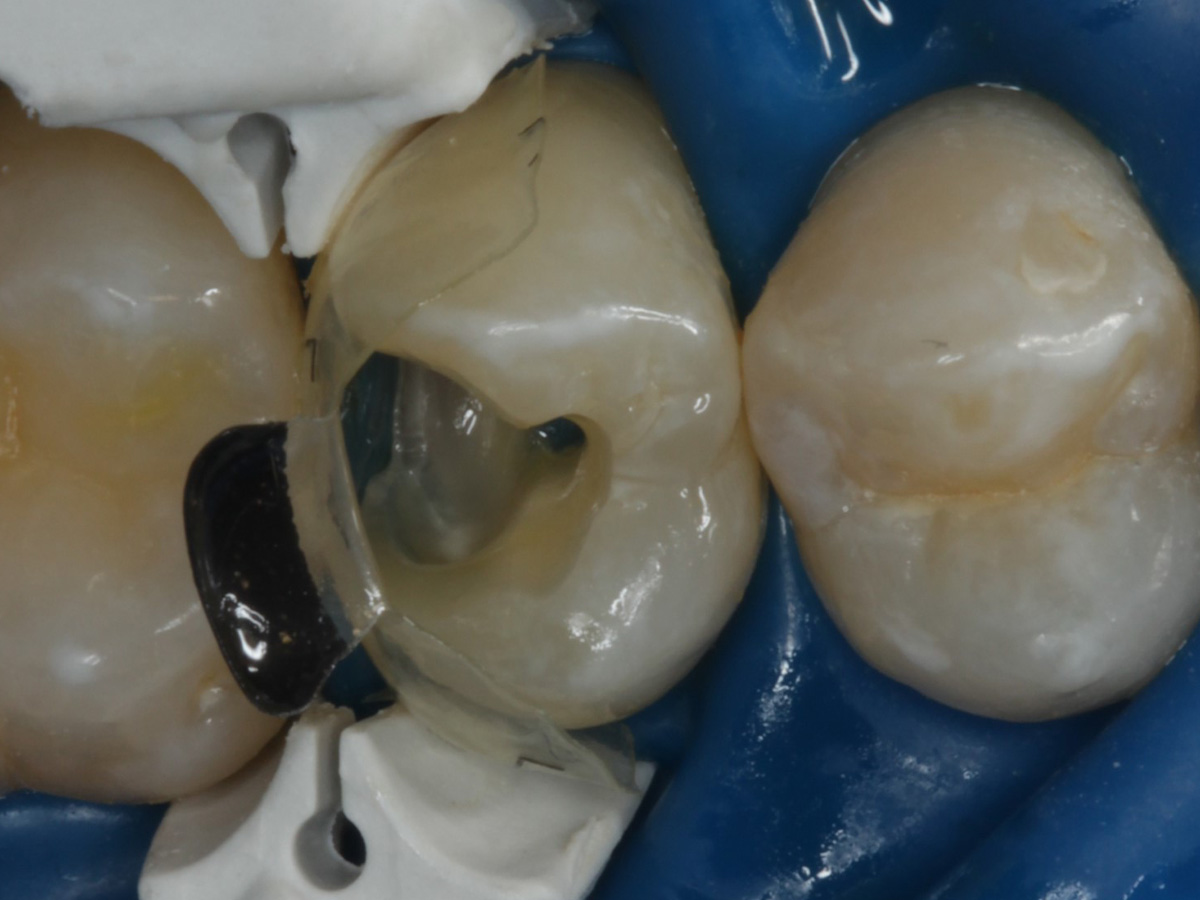

Abbildung 2

Intakte Kaufläche